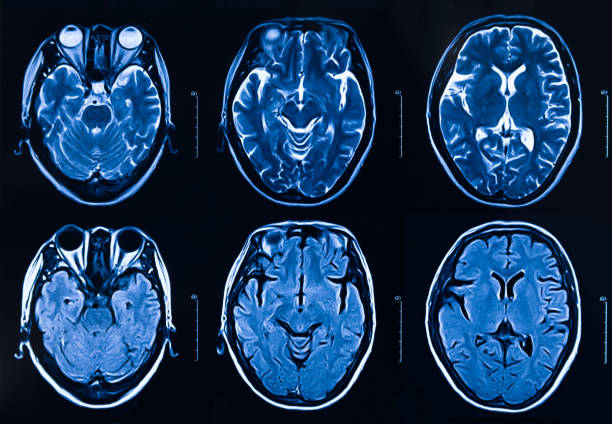

本研究納入2018年1月1日至2020年10月31日發(fā)病168小時內(nèi)發(fā)生急性ICH的患者。間充質(zhì)干細胞被靜脈注射給9名患者(5名女性,4名男性),平均年齡(范圍)為61(36-84)歲。表1總結了人口統(tǒng)計學和臨床??特征 。出于描述目的,患者按照入組順序獲得編號,并連續(xù)分配到三組中的一組,每組三人。根據(jù)模型 2 分割,ICH體積范圍為0.1至54.9mL(平均ICH體積為23.5mL)。5例ICH累及局部腦葉,其余則位于基底節(jié)或外囊深處。在三名患者中,ICH位于丘腦(圖1),在一名患者中,血腫位于多個腦結構(即尾狀核、殼核和蒼白球)。平均而言,MSC在ICH后3天進行注射。